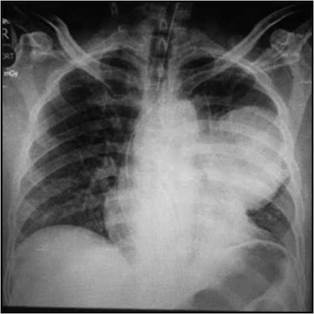

Al tercer día el paciente presenta de manera súbita pérdida del estado de conciencia en sala de quimioterapia, le documentan ausencia de pulso y activan protocolo de resucitación de la institución por lo que el servicio de emergencias acude a la sala de oncología. Se encuentra a un paciente con esfuerzo respiratorio agónico, monitorizado y con la presencia de taquicardia ventricular que progresa a asistolia, se procede a intubación en secuencia crash sin complicaciones, se realizan maniobras de resucitación por aproximadamente 20 minutos y se logra retorno a circulación espontánea, se documenta en ultrasonido a la cabecera del paciente derrame pericárdico sin evidencia de taponamiento, con pobre contractilidad, se descarta hemo o neumotórax, las cavidades cardiacas se encontraron de tamaños usuales, se realiza electrocardiograma (EKG) el cual documenta lesión subepicárdicas de la cara anterior, la cual no era conocida en EKG previo (Figura 1), se le da aviso a grupo de hemodinamia y se traslada a sala de procedimientos angiográficos donde realizan arteriografía coronaria de emergencia, que reporta coronarias epicárdicas sin evidencia de placas arterioescleroticas; sin embargo, en la arteria descendente anterior reportan que "se observan ramas anteriores hacia una estructura que no se logra identificar en el aspecto más anterior, superior y proximal de la arteria y que podría corresponder a pequeñas fístulas a un hemangioma o irrigación de estructura neoplásica infiltrante" (Figura 2), se hace ecocardiograma posparo que documenta deterioro de la eyección a 35% con aquinesia anterior tercio distal y con imagen compatible con trombo apical, con derrame pericárdico moderado sin evidencia de taponamiento cardiaco. Así mismo se obtuvo una radiografía de tórax pos paro donde es evidente la masa mediastinal (Figura 3).